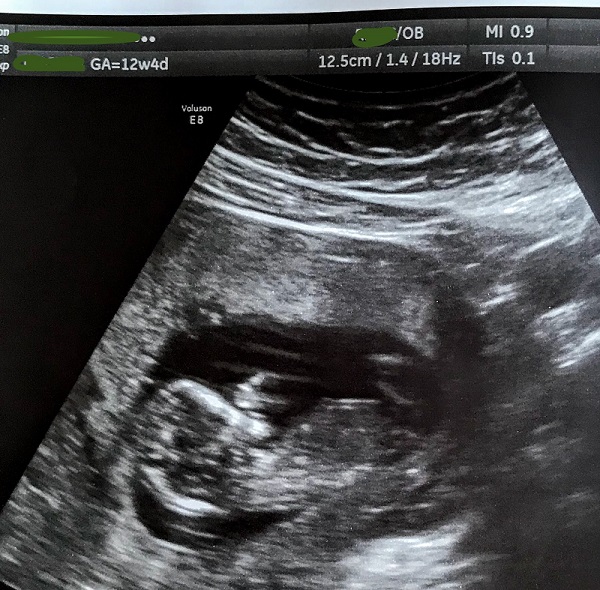

I had an ultrasound at 12w5d and I *think* I have a guess as to whether the baby is a boy or girl - could you please let me know what you think?

Cant see a nub in those pics sorry. Do you have any more?

No, these are my only pics, unfortunately. I'm hoping that something can be discerned from the 3D shot, between the legs?

Sorry, no nub. Boy and girls look the same between the legs at this stage.